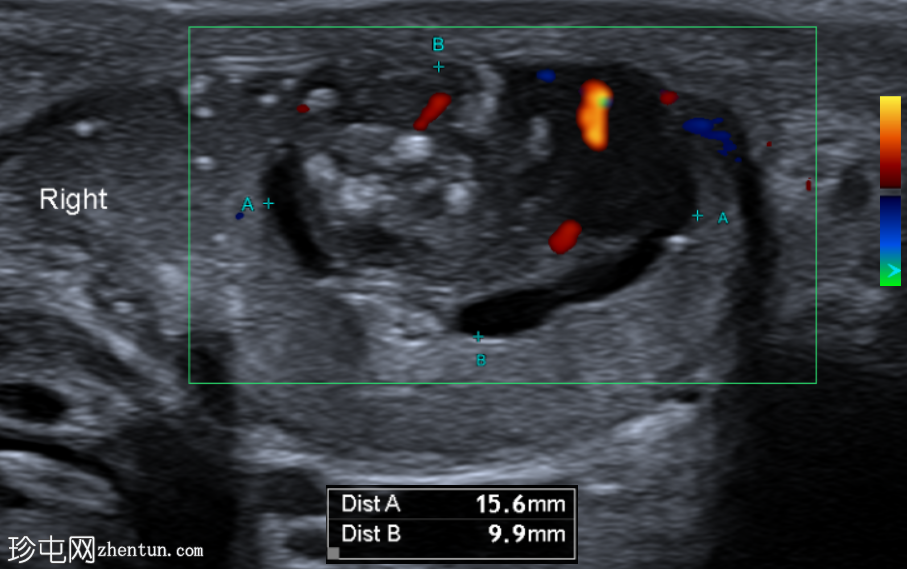

超声检查

右侧睾丸内可见一异质性肿块,大小约10 x 14 x 15 mm,包含实性和囊性成分。肿块内可见多发小钙化灶。彩色多普勒超声检查显示肿块内血流信号较少。